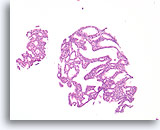

Papillair neoplasma, Borst FNA, Celblok.

Een kleine vergroting van de residuele naaldspoeling van de patiënt in afbeelding 39-42 toont een duidelijk papillaire architectuur. Let op de gelijksoortigheid van de ductale populatie in dit hele veld. Dit monotone patroon duidt meer op een papillair carcinoom dan een papilloom.

40X

Papillair neoplasma, Borst FNA, Celblok.

Een kleine vergroting van de residuele naaldspoeling van de patiënt in afbeelding 39-42 toont een duidelijk papillaire architectuur. Let op de gelijksoortigheid van de ductale populatie in dit hele veld. Dit monotone patroon duidt meer op een papillair carcinoom dan een papilloom.

40X

Papillair carcinoom, Borst FNA, Celblok.

Sterkere vergroting van de patiënt uit afbeelding 39-43 toont een fibrovasculaire kern (open pijl) en een cribriform gebied dat consistent is met een papillair carcinoom (pijl).

10X

Papillair carcinoom, Borst FNA, Celblok.

Sterkere vergroting van de patiënt uit afbeelding 39-43 toont een fibrovasculaire kern (open pijl) en een cribriform gebied dat consistent is met een papillair carcinoom (pijl).

10X

Papillair carcinoom, Borst FNA, Celblok.

Een ander cribriform gebied (pijl) en een fibrovasculaire kern (open pijl) kunnen gemakkelijk worden onderscheiden.

10X

Papillair carcinoom, Borst FNA, Celblok.

Een ander cribriform gebied (pijl) en een fibrovasculaire kern (open pijl) kunnen gemakkelijk worden onderscheiden.

10X

Papillair carcinoom, Borst FNA, Celblok.

Een sterkere vergroting van het diagnostische cribriforme patroon in afbeelding 45 toont een monotone celpopulatie met gerandomiseerde polariteit die gladde, ronde ruimten vormt. Necrotisch materiaal is focaal aanwezig in één lumen.

40X

Papillair carcinoom, Borst FNA, Celblok.

Een sterkere vergroting van het diagnostische cribriforme patroon in afbeelding 45 toont een monotone celpopulatie met gerandomiseerde polariteit die gladde, ronde ruimten vormt. Necrotisch materiaal is focaal aanwezig in één lumen.

40X